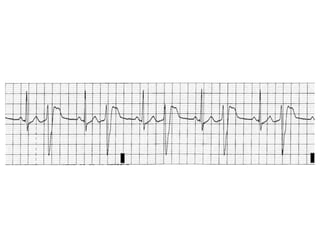

Electrocardiogram

• Almost any cardiac dysrhythmia may be observed in

digoxin toxicity.

• The most common arrhythmias in digoxin toxicity

are PVCs and Bradyarrhythmias.

• Ventricular dysrhythmias occur more frequently in

chronic than in acute poisonings.

ECG findings therapeutic levels

– T-wave changes (such as flattening/inversion/Biphasic T

waves),

– QT-interval shortening,

– “Scooped” or “Salvador Dali sagging” ST segment

depression, and

– Increased U-wave amplitude

ECG finding at toxic level

• Frequent PVCs ( the most common abnormality),

including ventricular bigeminy and trigeminy.

• Sinus bradycardia

• Slow Atrial Fibrillation

• Any type of AV block ( 1st degree,2nd degree & 3rd

degree)

• Ventricular tachycardia, including polymorphic and

bidirectional VT